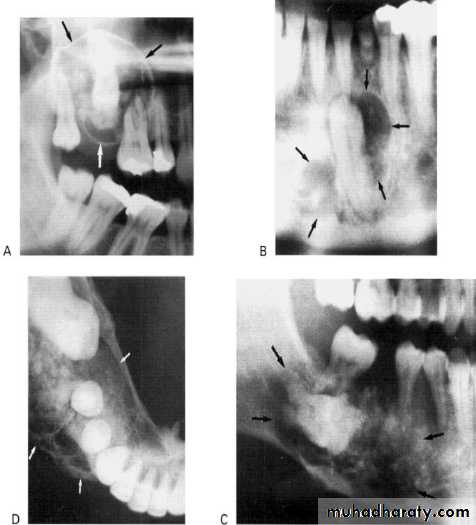

Secondary infection of broken roots produces a partly radiolucent and partly radiopaque (mixed) lesions. The clinical history, location, and appearance of radiopaque area is assist in arriving at the correct diagnosis.Cystic odontoma

The compound and complex odontoma are lesion of slow growth and are radiopaque, on rare occasions one of them may undergo a cystic changer. Under these circumstances a odontoma is surrounded by a radiolucency and called cystic odontomaCalcifying Epithelial Odontogenic Tumors (CEOT), Pindborg Tumors

This rare odontogenic tumour usually presents in the premolar/molar region of the mandibleAppearance: They can be either monolocular or multilocular, but tend to remain relatively small although they can cause expansion of surrounding cortical bone. They are often associated with an unerupted tooth.

Outline: The lesion tends to be of variable definition and cortication but is frequently scalloped.

Radiodensity: They are often radiolucent in their early stages; then numerous scattered radiopacities usually become evident within the lesion, often most prominent around the crown of any associated unerupted tooth. This appearance is sometimes described as driven snow.